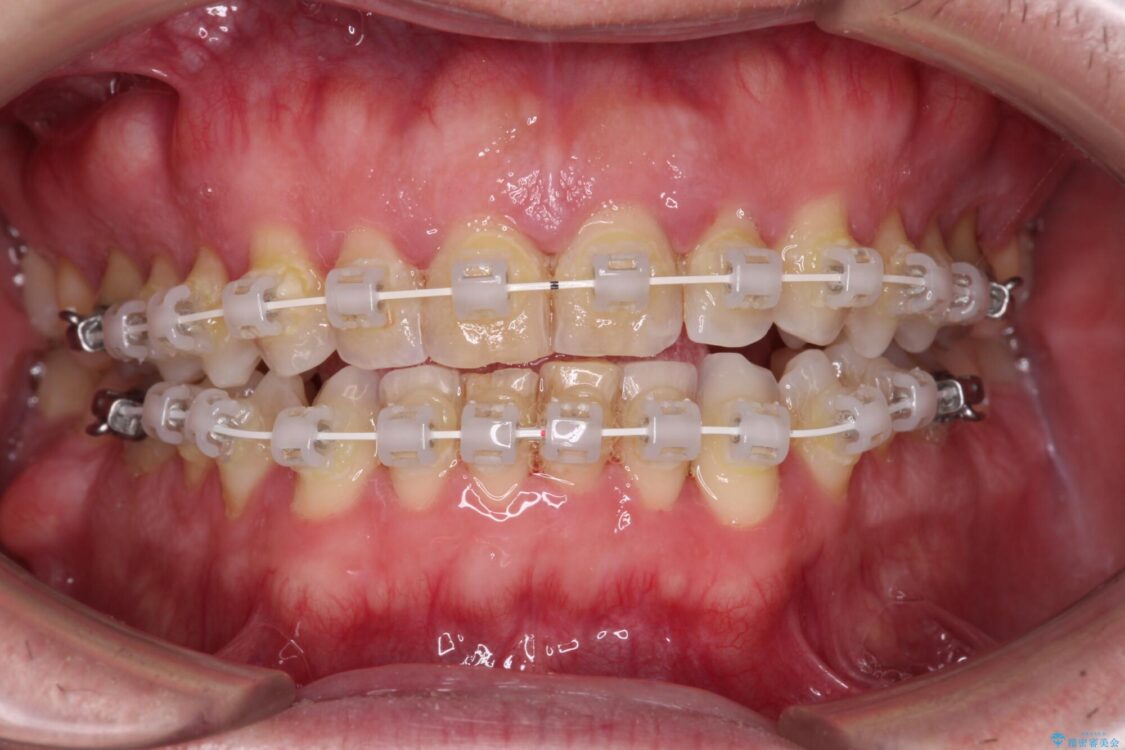

前歯の非接触改善は、インビザラインの得意とするところですが、マウスピース矯正は絶対に継続できないとのことで、ワイヤー装置にて矯正治療を行うこととしました。

治療途中

• 前歯でものを噛みきりたい 目立たない装置でのワイヤー矯正 治療途中画像